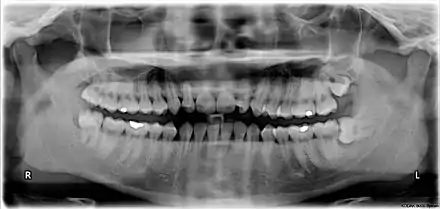

The third molar, commonly called wisdom tooth, is the most posterior of the three molars in each quadrant of the human dentition. The age at which wisdom teeth come through (erupt) is variable,[1] but this generally occurs between late teens and early twenties.[2] Most adults have four wisdom teeth, one in each of the four quadrants, but it is possible to have none, fewer, or more, in which case the extras are called supernumerary teeth. Wisdom teeth may become stuck (impacted)[3] against other teeth if there is not enough space for them to come through normally. Impacted wisdom teeth are still sometimes removed for orthodontic treatment, believing that they move the other teeth and cause crowding, though this is not held anymore as true.[4][5]

Wisdom teeth (often notated clinically as M3 for third molar) have long been identified as a source of problems and continue to be the most commonly impacted teeth in the human mouth. Impaction of the wisdom teeth results in a risk of periodontal disease and dental cavities.[24] Impacted wisdom teeth lead to pathology in 12% of cases.[25]